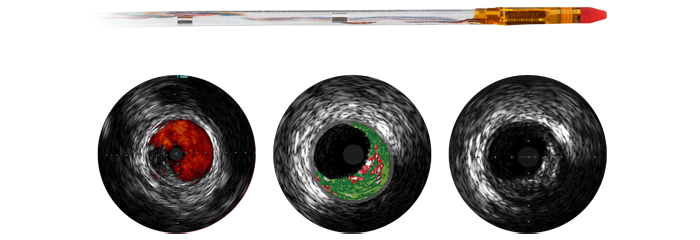

À medida que mais pacientes com CAD são considerados para terapia de intervenção minimamente invasiva, o planeamento de tratamento ideal é prejudicado pelo facto de a angiografia coronária 2D ter limitações na deteção e avaliação da estenose coronária. Os dados não são ligados de forma consistente e significativa antes e durante o procedimento, o que acrescenta tempo e complexidade ao planeamento de tratamento. Concebemos as nossas soluções de cardiologia para superar estes desafios, para que possa perceber os benefícios da eficiência clínica no laboratório de cateterismo:

A terapia guiada por imagens, iFR, IVUS e monitorização hemodinâmica, bem como o planeamento pré-procedimento cardíaco e aplicações avançadas, estão todos ligados à interface de terapia guiada por imagens para permitir a visualização, manipulação e configuração personalizada no monitor a partir de um único controlador ao lado da mesa ou a partir da sala de controlo.